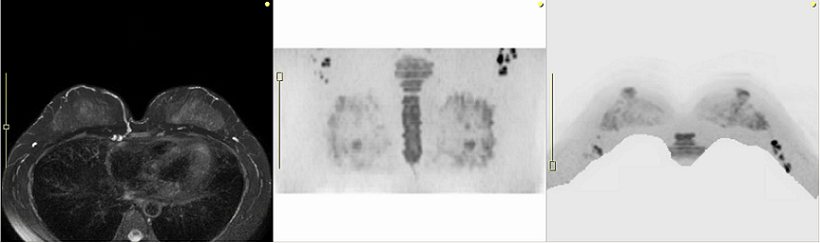

DWIBS法

DWIBS法による撮影画像